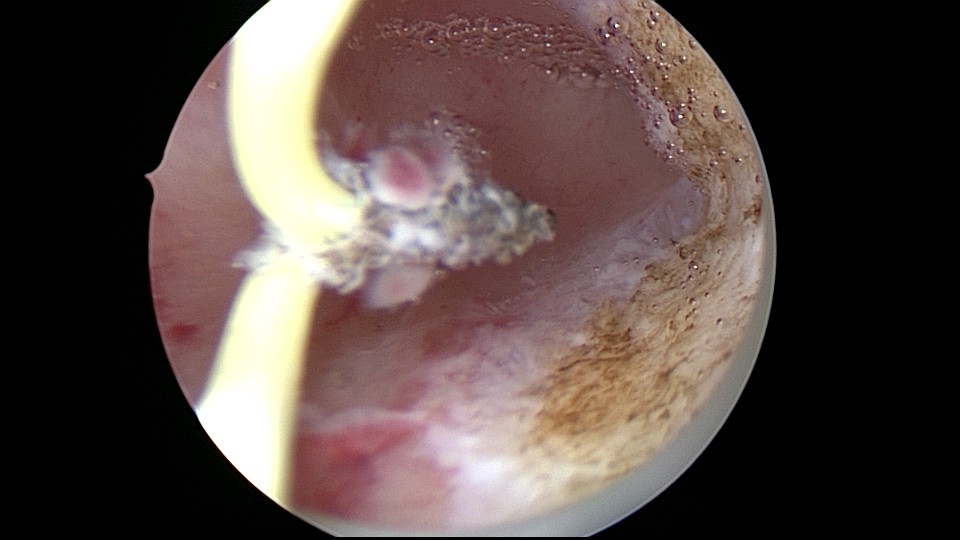

患者35岁,G5P0,继发不孕10年,10年前外院开腹宫外孕手术1次,试管失败1次。外院B超提示宫腔粘连,2021年4月在成都西囡妇科医院做宫腔镜检查,发现宫腔粘连。2021年11月到我院做宫腔镜分粘手术,术中见宫腔两侧及右侧宫角致密粘连,内膜片状充血,单极电切分粘,恢复宫腔形态,显露双侧输卵管开口。2021年12月宫腔镜二探取球囊,宫腔形态正常,双侧输卵管开口可见。分粘后再次试管成功,足月分娩。现40岁,G6P1。